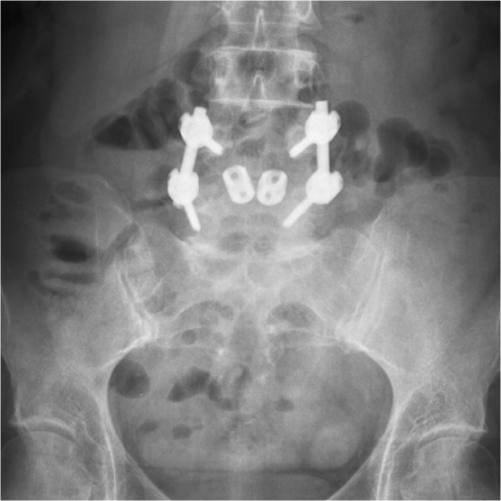

Radiografie din incidenţa laterală ce demonstrează spondilolisteza L4-L5 la o pacienta în vârstă de 54 ani